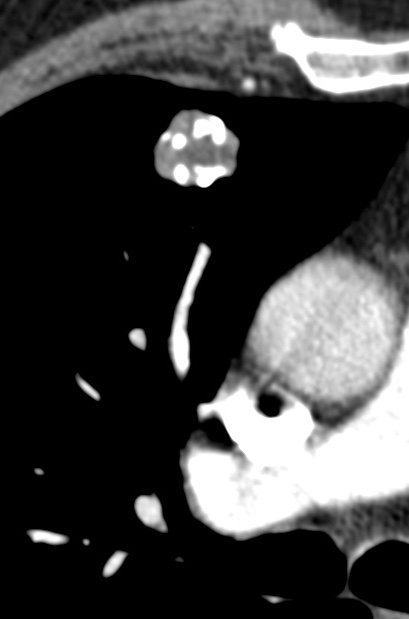

Radiology description

- Small coin lesion, often solitary, characterized by smooth edge, focal fat or fat alternating with calcific foci (Ann Thorac Med 2015;10:231)

- Calcifications often described as popcorn calcification

- Intralesional fat and popcorn-like calcifications allow a confident diagnosis on CT (J Thorac Imaging 2016;31:11)